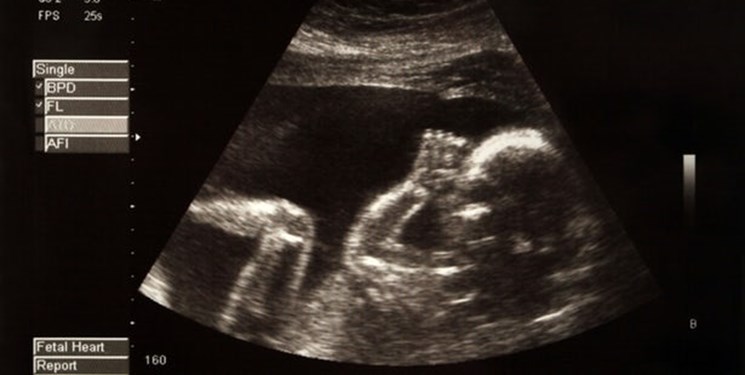

محققان فرانسوی با تصویربرداری سه بعدی از مغز جنین انسان برای اولین بار موفق شدند از تغییرات مغز نوزادان تا زمان تولد با دقت و جزئیاتی بی سابقه مطلع شوند.

پزشکان به خوبی می دانند که مغز جنین از انعطاف پذیری خاصی برخوردار است که تولد و خروج آن از رحم مادر را بدون وقوع مشکل حادی ممکن می‌کند. اما اطلاع از جزئیات این تغییرات تا به امروز ممکن نبوده است. تصویربرداری سه بعدی مغز با دقتی استثنایی کسب اطلاع از این تغییرات جزئی را ممکن کرده است.

این تصویربرداری بررسی لحظه به لحظه تغییر شکل جنین در زمان عبور از رحم مادر را ممکن کرده و نشان می دهد در هر لحظه از این رویداد مغز جنین چه تحولاتی را پشت سر می گذارد.

اسکن یادشده با استفاده از یک دستگاه پیشرفته ام آر آی صورت گرفته و بین هفته های 36 تا 39 دوره حاملگی رخ داده است. این تصویربرداری سپس در زمان آماده شدن جنین برای خروج از رحم تکرار شده است.

نکته جالب اینکه نتایج این بررسی علمی حتی برای پزشکان آشنا به فرایند مذکور نیز جالب و شگفت انگیز بوده است. زیرا در تمامی موارد استخوان های جمجمه مغز جنین ها کاملا فشرده شده بودند که این امر نشان دهنده شدت فشاری است که به سر نوزاد در حین تولد وارد می شود. اما این فشار باعث آسیب مغزی به آنها نمی شود.